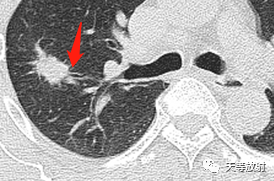

囊腔型腺癌CT病例解读。男性,64岁

2020.6.10

右肺上叶结节影,周围更小结节,形态不规则,胸膜面相对干净。